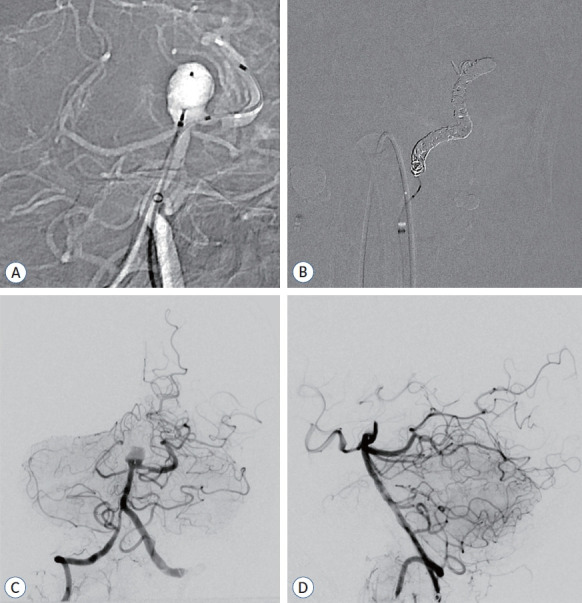

由于巨型部分血栓形成的颅内动脉瘤的自然病史并不乐观,而且缺乏标准化的治疗方法,因此治疗这类动脉瘤面临着巨大的挑战。传统的治疗方法,无论是开放手术还是血管内治疗,往往难以有效控制这些动脉瘤,导致高复发率或严重的发病率。患者是一名 62 岁的男性,基底动脉顶端有一个无症状的部分血栓形成的巨大动脉瘤,表现为左侧偏瘫和构音障碍。诊断成像显示该动脉瘤为巨型动脉瘤,宽颈、管状部分。为了最大限度地保障患者安全,患者接受了两阶段血管内治疗,包括球囊闭塞试验(BOT)和术中监测(IOM)。治疗采用了支架辅助编织内桥(WEB)栓塞和连续双侧椎动脉夹闭。手术成功分离了动脉瘤,术后成像证实没有再堵塞,保留了完整的后循环。患者在 12 个月的随访期间恢复稳定,未出现神经功能障碍。本技术报告展示了使用 WEB 装置和通过双侧椎动脉夹闭逆转血流治疗巨大的部分血栓动脉瘤的可行性和有效性。

Managing giant partially thrombosed intracranial aneurysms presents significant challenges due to their unfavorable natural history and the lack of standardized treatment approaches. Conventional treatments, whether open surgical or endovascular, often struggle to manage these aneurysms effectively, resulting in high recurrence rates or significant morbidity. The patient was a 62-year-old male with a symptomatic giant partially thrombosed aneurysm at the tip of the basilar artery, presenting with left-sided hemiparesis and dysarthria. Diagnostic imaging revealed a giant aneurysm with a wide-necked, canalized portion. A two-stage endovascular treatment was conducted, involving a balloon occlusion test and intraoperative monitoring for maximum patient safety. The treatment utilized stent-assisted Woven EndoBridge (WEB) embolization and serial bilateral vertebral artery trapping. The procedure successfully isolated the aneurysm and postoperative imaging confirmed the absence of recanalization, preserving the intact posterior circulation. The patient showed stable recovery and no neurological deficits during the 12-month follow-up period. This technical note demonstrates the feasibility and efficacy of strategically integrating intrasaccular flow diversion using a WEB device and flow reversal through bilateral vertebral artery trapping for treating giant partially thrombosed aneurysms.